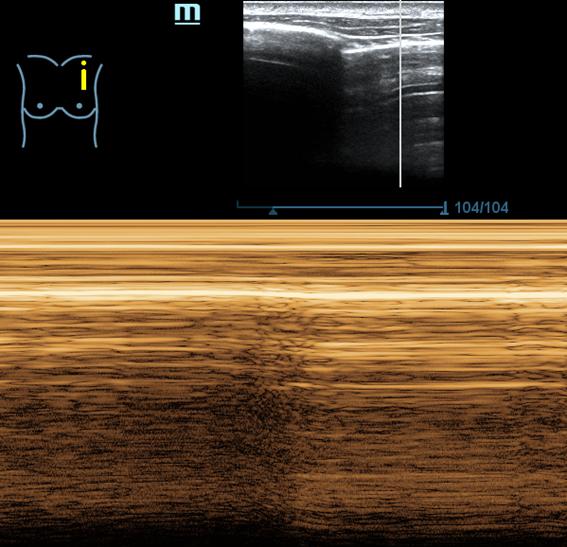

- Ecografía pulmonar (protocolo BLUE): Perfil A en los 4 puntos BLUE anteriores: deslizamiento pleural y líneas A. Signo de la playa en modo M. Puntos PLAPS: deslizamiento pleural, irregularidades pleurales, >2 líneas B.